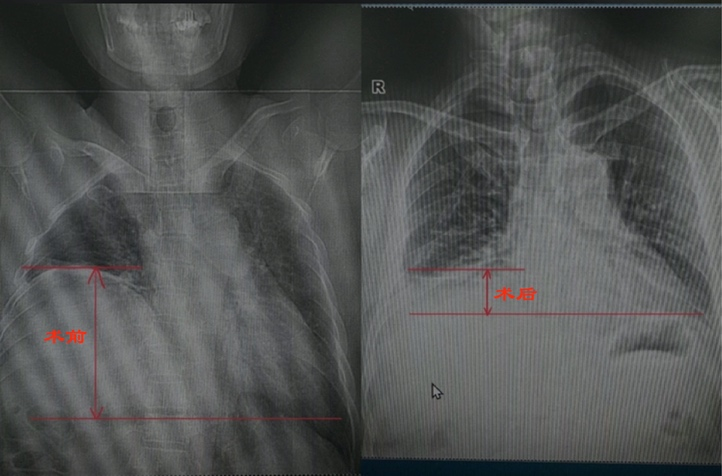

王女士长期受气短困扰,爬两层楼就需停下休息,多次就诊均未找到病因。直到在绵阳市第三人民医院行胸部CT检查,才发现左侧膈肌明显抬高,肺组织受压。普通外科团队为其施行了腹腔镜下膈肌折叠术。手术创伤小、恢复快,术后王女士呼吸顺畅,活动能力显著改善:“终于能正常走路、上下楼了,以前还以为是自己年纪大了体质变差。”

A:胸部X线片可见膈肌抬高,CT或MRI可进一步评估膈肌形态与周围结构,必要时结合肺功能检查及神经肌电图。